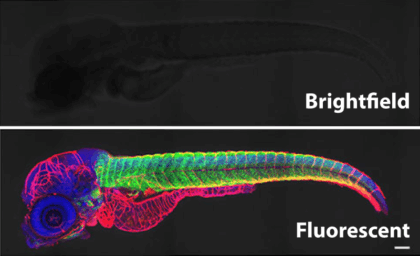

Now immunofluorescence is an indispensable technique for locating proteins and other molecules within cells. Here, a many-color “multiplex” format distinguishes several cell types in the tumor microenvironment of esophageal cancer.